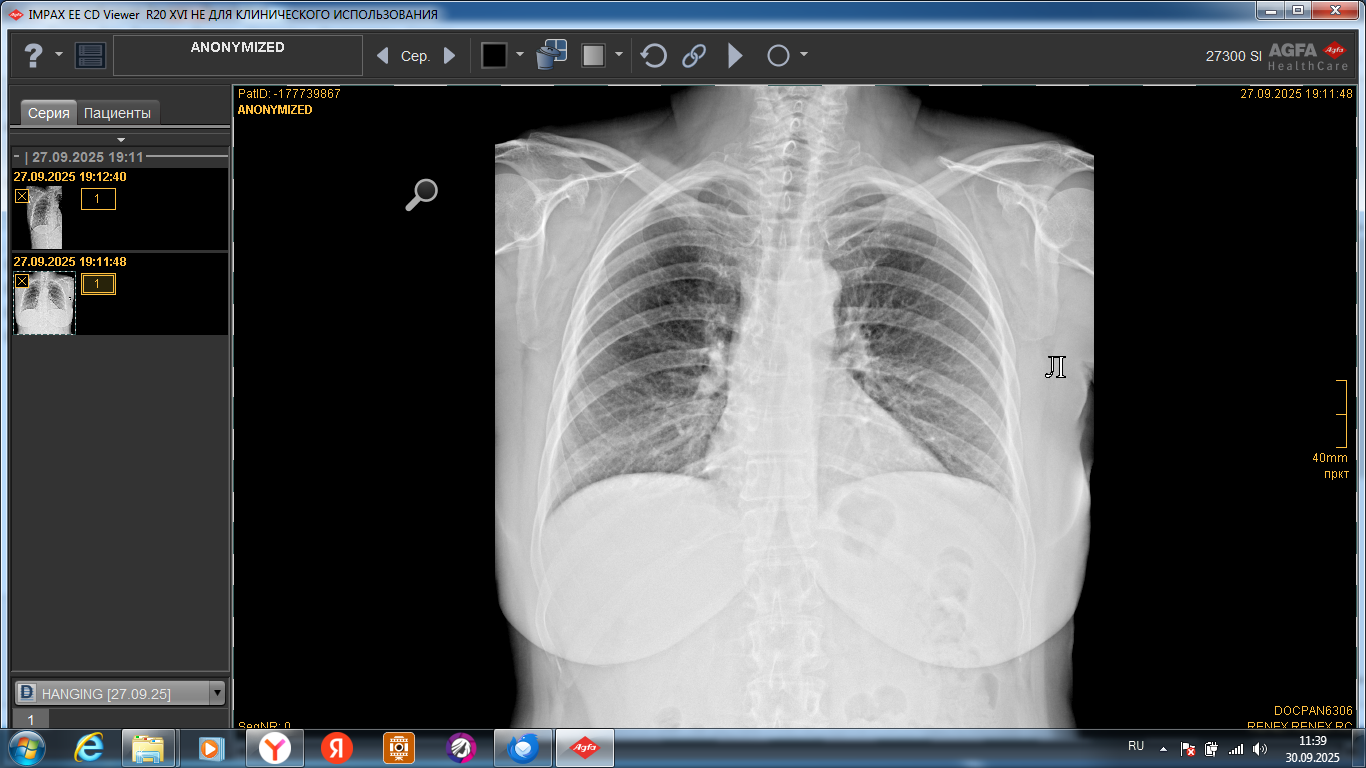

Вывих правой стопы снаружи и сзади, перелом обеих лодыжек и заднего края большеберцовой кости правой голени

Коленный сустав

Боли в коленном суставе